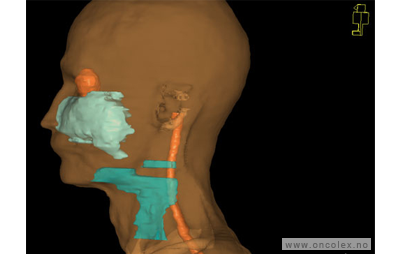

Skisse over hvordan strålefeltet planlegges:

Illustrasjon for målvolum

• GTV (Gross Tumor Volume): Identifisert tumor.

• CTV (Clinical Target Volume) GTV + omkringliggende vev hvor det kan væremikroskopisk spredning.

• ITV (Internal Target Volume): CTV + en indre margin som tar hensyn tilindre bevegelser og endringer av CTV.

• PTV (Planning Target Volume): Innstillingsmargin som inneholder ITV og samtidig tar hensyn til antatte pasientbevegelser, samt variasjoner i pasientopplegging og feltinnstillinger.

• Feltgrense. Tegnes som oftest på kroppen.